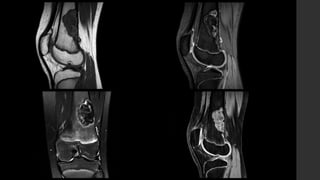

Tumor de Células Gigantes.

• Se localizan en huesos largos y sólo en núcleos de osificación cerrados, cercanos a

la superficie articular (84 – 99% <1cm).

• Son lesiones bien definidas excéntricas con margen no esclerótico.

• RX y TC 

 Zona de transición delgada sin esclerosis periférica.

 La corteza adyacente está adelgazada, expandida o deficiente.

 Reacción perióstica sólo en 10 - 30% de los casos.

 Puede presentar masa de tejidos blandos.

 Puede haber fracturas patológicas.

 No presentan matriz calcificada.

• IRM 

 T1 

 Componente sólido con señal intermedia a baja.

 Periferia con señal baja.

 T1+C 

 Realce de los componentes sólidos (lo distingue del quiste óseo aneurismático).

 Puede mostrar realce en la médula ósea adyacente.

 T2 

 Señal alta heterogénea con áreas de señal baja (debido a hemosiderina y fibrosis).

 Si hay componente quístico óseo aneurismático puede mostrar niveles líquido – líquido.

 Si hay señal alta adyacente a la médula ósea puede deberse a edema.